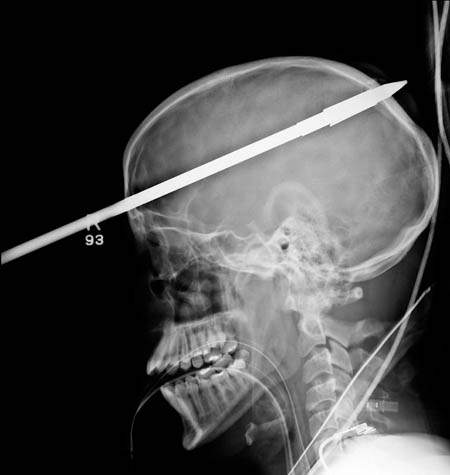

貫通16歲少年頭部的魚叉

圖片來自:http://www.po-kaki-to.com/